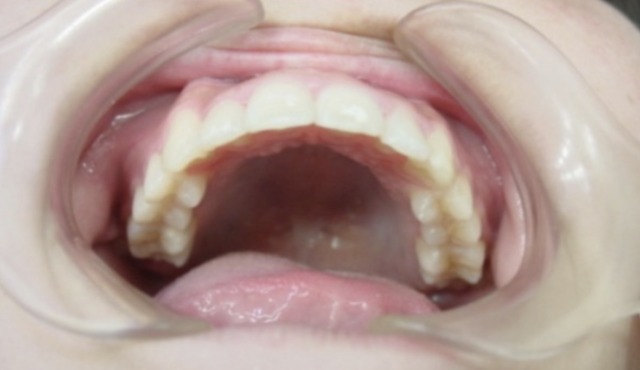

After

| 症状 | 上顎前歯の右側転位のために、右側2番の舌側転位と右側3番(犬歯)の萌出スペースなし。 |

| 処置内容 | 1期治療 プレート拡大装置 2期治療 マルチブラケット装置(右上7番抜歯してそこに右上8番親知らずを誘導した。) |

| デメリット・院長コメント | 永久歯を抜かない治療のデメリットは、治療期間が長いことです。ただし、その後の人生の長さを考えると、健全な小臼歯を2本または4本抜歯の矯正治療よりも、はるかにメリットがあるといえます。また、アーチが小さくならないので、舌が後ろに押し込まれないためいびき防止につながり睡眠の質の向上にもつながります。 |